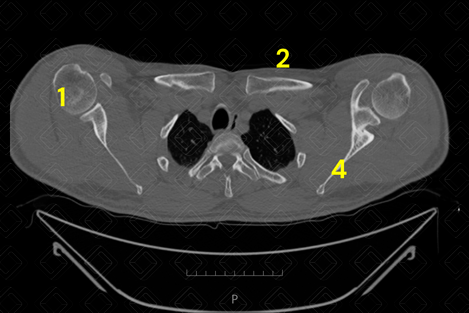

Texto alternativo para a imagem Figura 1. Tomografia computadorizada dos ombros - plano axial. Créditos: Athena Hub/Medical Harbour

Legenda: 1 = úmero; 2 = clavícula; 3 = acrômio; e 4 = escápula.